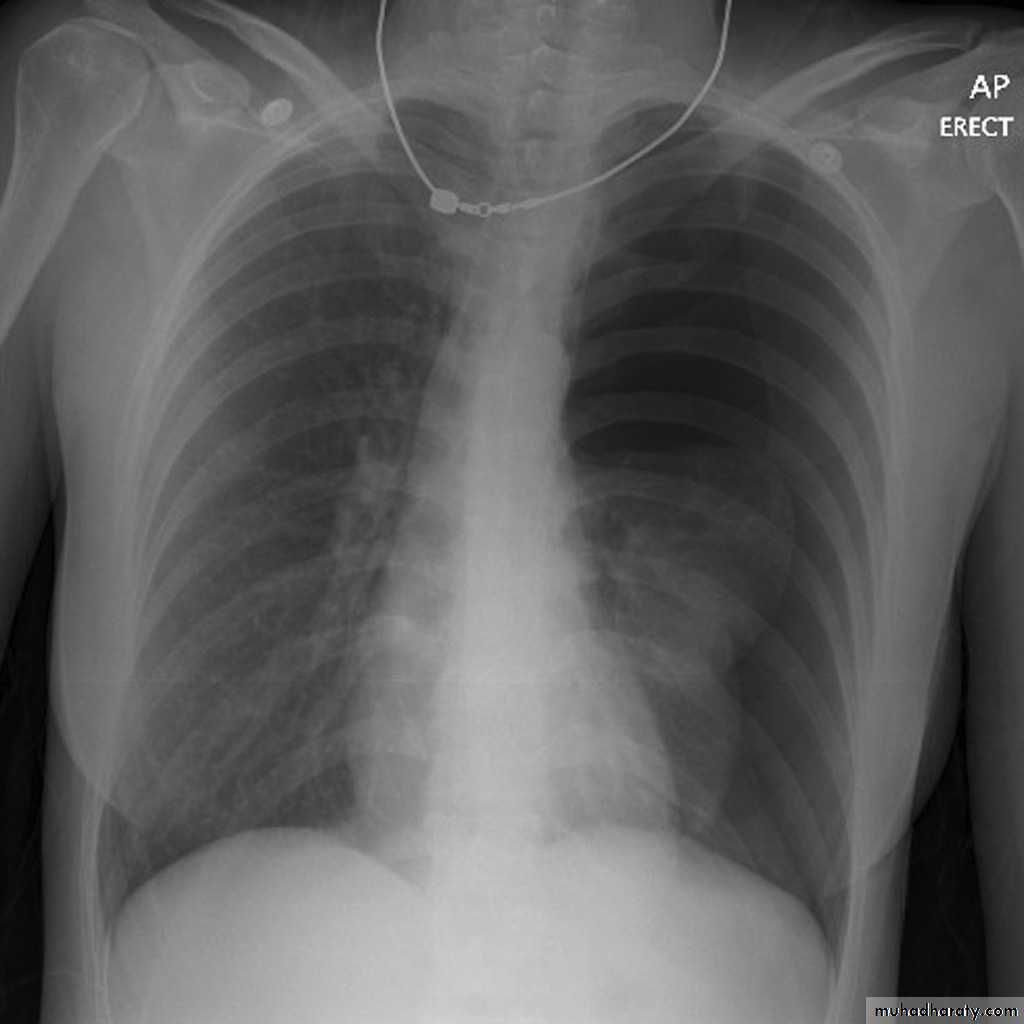

Patient with fever, rigor and dyspnea